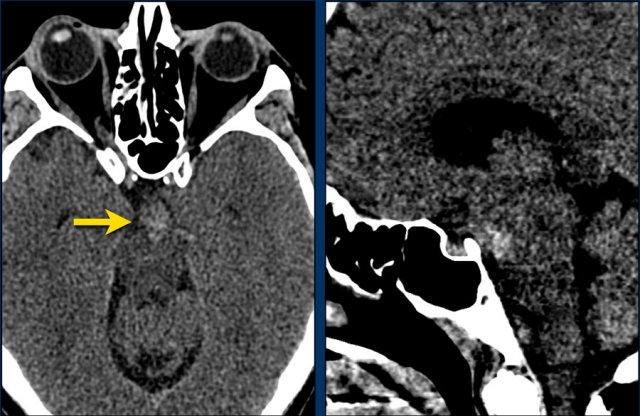

Bệnh nhân này nhập viện với não úng thủy do xuất huyết não thất (hình bên trái).

Lưu ý vùng tăng tỷ trọng rất nhỏ tại đồi thị trái, là điểm khởi phát của xuất huyết.

Theo dõi một ngày sau (hình bên phải).

Bệnh nhân được phẫu thuật đặt dẫn lưu não thất để điều trị não úng thủy.

Lưu ý đồi thị bên trái giảm tỷ trọng với ổ tăng tỷ trọng dai dẳng ở vị trí trong.